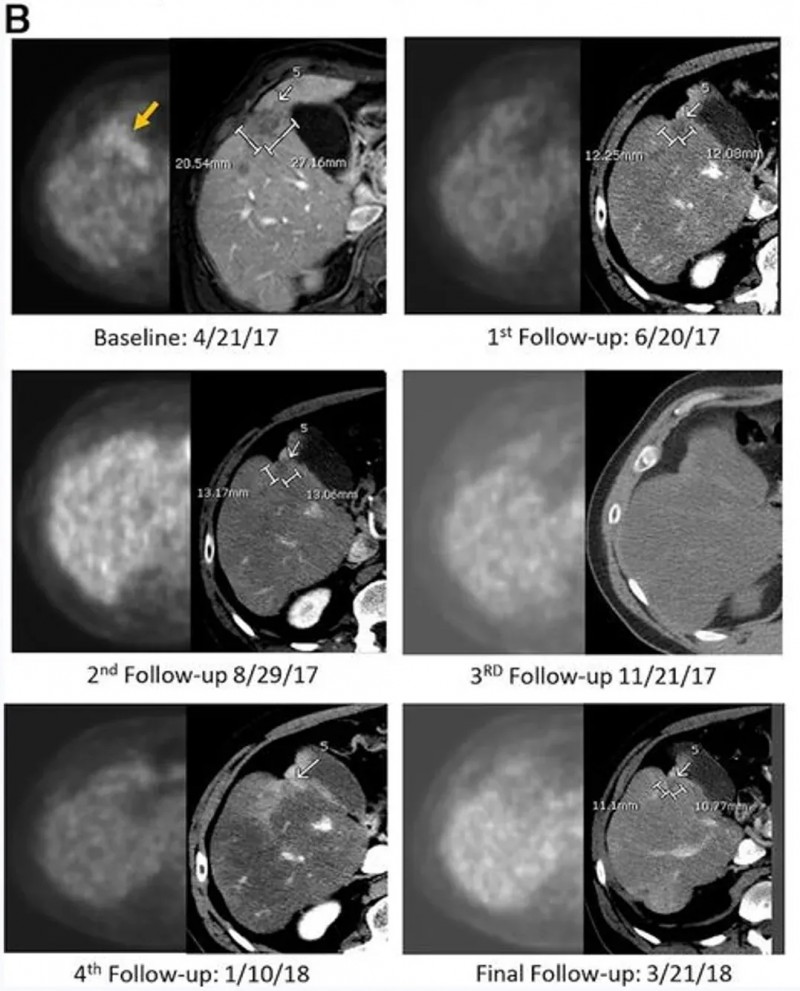

结果显示:CAR-T输注6周后,正电子发射断层扫描(PET-CT)提示肝脏内原氟脱氧葡萄糖(FDG)阳性病灶完全无代谢活性,该完全代谢反应持续13个月;静脉增强CT显示目标病灶稳定或略缩小,无新增转移灶。治疗3.7个月时,PET扫描显示肝脏仍维持无代谢活性,但胰头原发灶代谢活性升高,患者随即接受胰腺肿块放疗(以5-氟尿嘧啶为放射增敏剂),后续扫描显示原发肿瘤灶亦达完全代谢缓解。该患者总生存期(OS)长达23.2个月——而多数IV期胰腺腺癌患者中位生存期仅5个月,意味着CEA CAR-T疗法让这位化疗耐药患者的生存期延长近5倍(4.64倍)。

在肿瘤标志物层面,以治疗中最低点计,患者癌胚抗原(CEA)下降81%、糖类抗原19-9(CA19-9)下降68%,且两类标志物均在治疗后2-3个月内恢复正常(详见下图)。病理分析显示,肝肿瘤活检标本出现大面积透明纤维化,无正常肝组织损伤迹象,且肿瘤标本中检测到大量CAR+细胞。